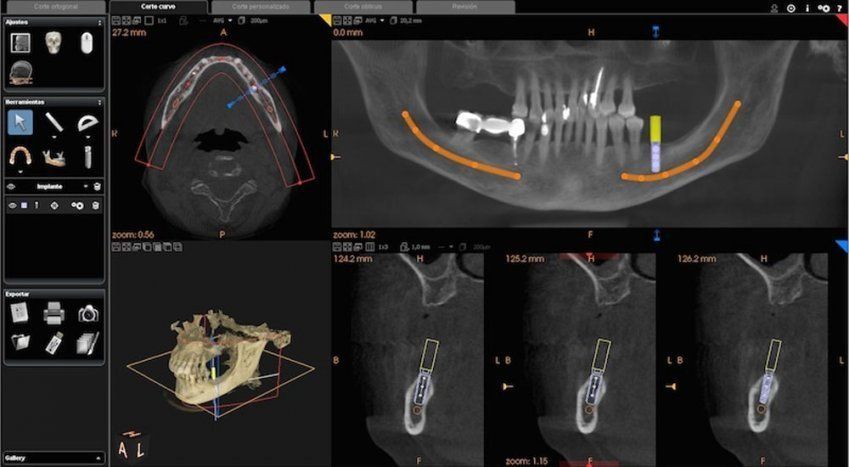

La precisión de esta prueba permite observar las estructuras dentales y maxilares en tres dimensiones, lo que facilita el diagnóstico y tratamiento

La radiografía Dentascan 3D permite ver, al detalle, cualquier estructura gracias a su procedimiento computarizado que une imágenes tridimensionales.

- Implantología. Con esta prueba conoceremos mejor la estructura ósea del paciente y asegurar así el éxito con la colocación del implante.